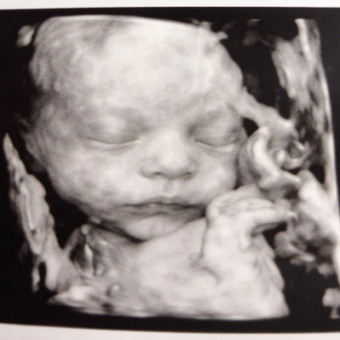

Oaklen Bruce Washburn due June 22nd! Woodland animal theme, love trees, foxes and the likes! Greens, oranges and natural colors/tones.